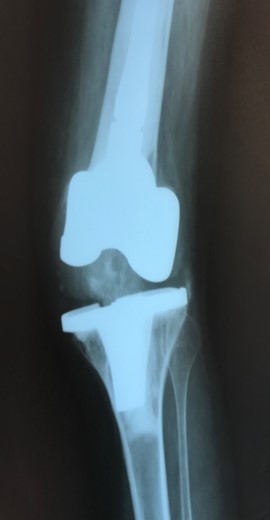

Приклад 1. Хвора Б. 52 років. Діагноз: Ревматоидній Деформівний IVст. гонартроз, вальгусна деформація колінногосуглоба.  Нестабільність та руйнування компонентів ендопротеза. Хворій виконано ревізійне ендопротезування: видалення компонентів ендопротезу, виявлений дефект латерального  виростку великогомілкової кістки тип Т3А за класифікацією АОRI [G.A. Engh, C.H. Rorabeck, 1997]. Під час операції виконана кісткова пластика дефекту латерального виростка лівої великогомілкової кістки. Використаний ендопротез колінного суглоба з подовжувачами .